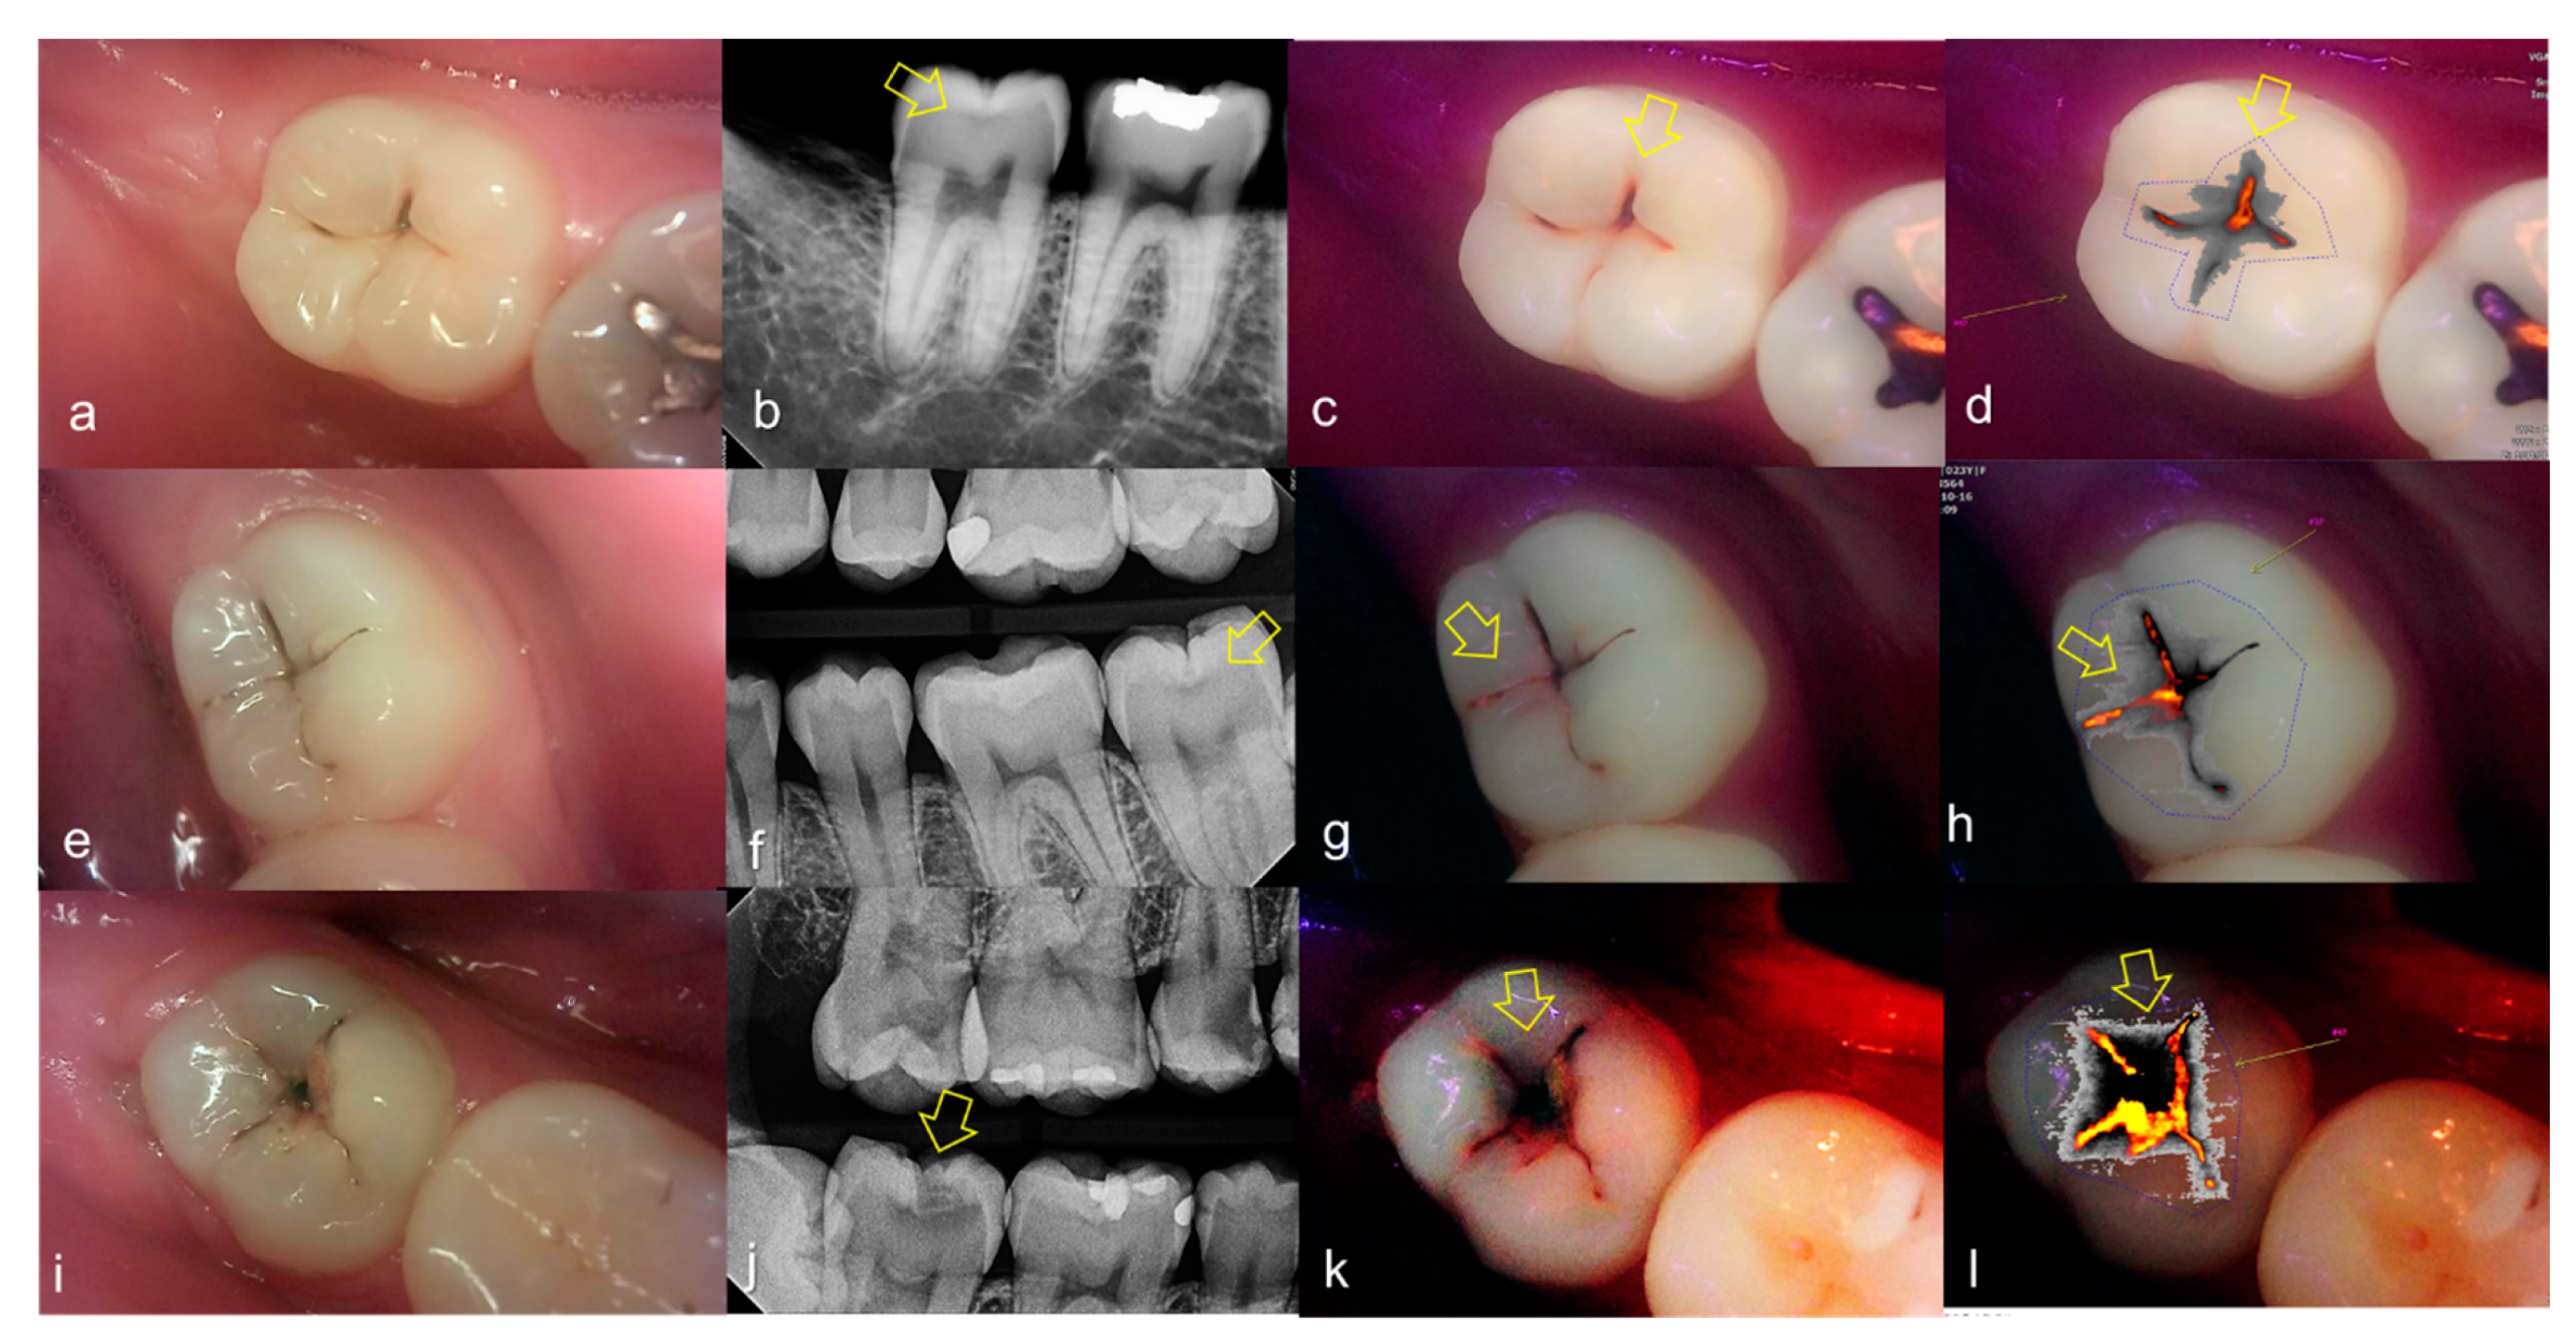

Representative images of QLF and bitewing radiograph of occlusal dental caries are shown in Figure 4 and Figure 5.

Figure 4.

Occlusal dental caries: (a–d) QLF caries score 1 (fluorescence loss and red fluorescence present as a line or spot in pits and/or fissures) and radiographic caries score 0 (no radiolucency visible) on #36; (e–h) QLF caries score 2 (fluorescence loss and red fluorescence glow extending around pits and fissures) and radiographic caries score 0 (no radiolucency visible) on #36; (i–l) QLF caries score 3 (red fluorescence glow extending around pits and fissures and a dark shadow from dentin present) and radiographic caries score 0 (no radiolucency visible) on #37; (a,e,i): white-light image of QLF; (b,f,j): fluorescence image of QLF; (c,g,k): bitewing radiograph; (d,h,l): analyzed QLF image using QA2 software.